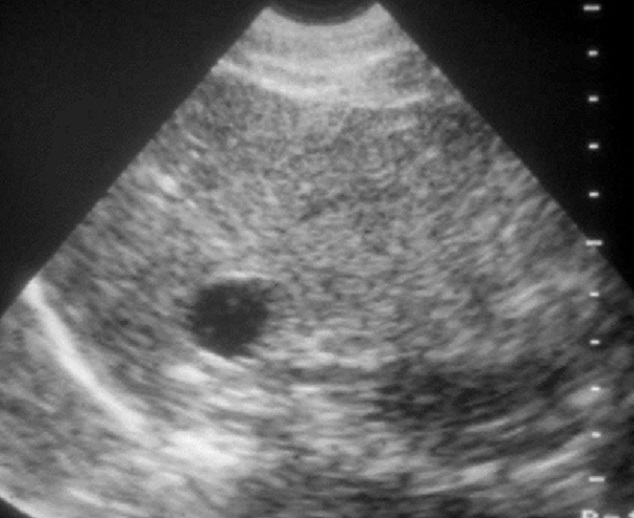

Image echographique

percutanée d'un kyste non parasitaire simple

endotheliale de la rate avec aspect echographique

lesionnel de kyste arrondie aechogen , a bord fine ,

nette avec cône de renforcement de l' acoustique

posterieure |